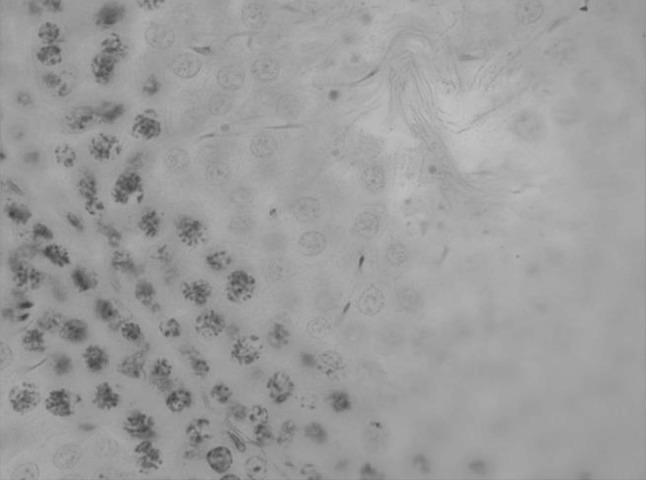

We have also carried out testis tissue histological examination of the animals affected by bichrome acute exposure. Cytological profile of the convoluted tubules’ spermatogenesis is represented in the Figs. 1, 2, 3, 4, 5, 6.

Testis convoluted tubules cross-section in preleptotene stage. H&E ×1000

Testis convoluted tubules cross-section in preleptotene and leptotene stage. H&E ×1000

Testis convoluted tubules cross-section in leptotene and zygotene stage. H&E ×1000

Testis convoluted tubules cross-section in zygotene stage. H&E ×1000

Testis convoluted tubules cross-section in pachytene stage. H&E ×1000

Testis convoluted tubules cross-section in diplotene and diakinesis stage. H&E ×1000

We have been also identifying prophase stages of the reduction division in the rats of the experimental and control group (Table 2). Comparison of the convoluted tubules’ average diameter of the control animals and the experimental group, showed diameter and lumen increase of the seminiferous tubules in the bichrome-exposed animals. Thus, convoluted tubules’ average diameter of the control animals was 263.72 ± 2.37 µm, convoluted tubules’ diameter of the experimental animals increased 10 % more, being 291.15 ± 3.11 µm. At that, sharp decrease of the spermatogenesis coefficient took place, which decreased by 68 %; also considerable increase of the number of tubules with “plugs” took place.